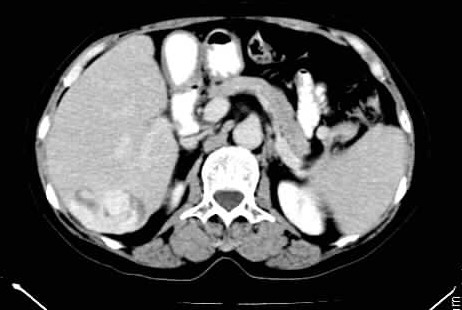

标题: CT24035:肝内占位

肝右叶后段低密度块影,增强后造影剂逐渐向病灶充填,支持肝血管瘤。

右叶后段血管瘤,层面少,看不见左叶,脾大。

肝右叶后段血管瘤、肝左叶缺如、脾大